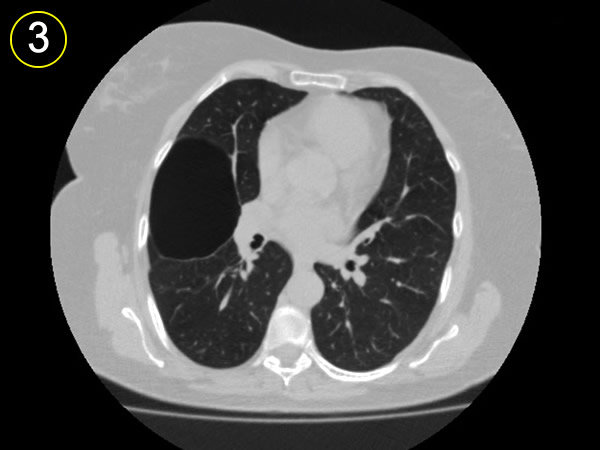

a-

segmento anterior del

lóbulo superior.

b-

lobulo medio

c-

segmento apical lobulo inferior

d-

bula subpleural